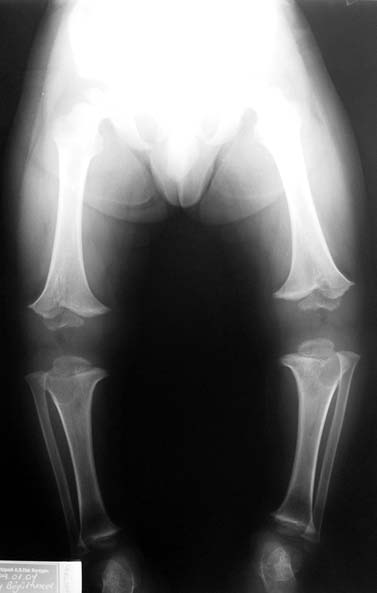

14 ve 16 yaşlar arasında her iki femurda toplam 10-12 cm boy uzatma her iki kalçanın fleksiyon deformitesinin düzeltilmesi (bu lomber hiperlordozu düzeltir) her iki kalçanın varus deformitesini düzeltme ortalama eksternal fiksasyon tedavi süresi = 10-12 ay

Vaka 3